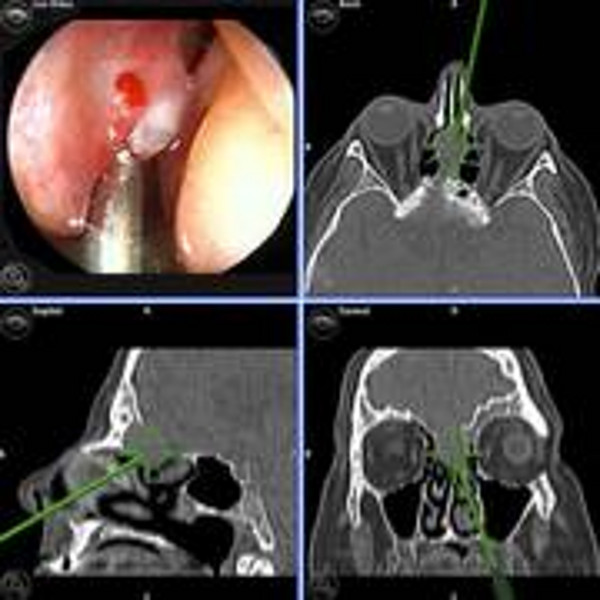

Karzinome der Nase, der Nasennebenhöhlen (NNH) und der Frontobasis können sich aus unterschiedlichen Geweben entwickeln und weisen so auch eine größere feingewebliche Varianz und ein unterschiedliches Wachstums- und Metastasierungsverhalten auf. Zu den häufigsten bösartigen Tumorarten rechnet man das Plattenepithelkarzinom, das anaplastische Karzinom, das Adenokarzinom oder das adenoidzystische Karzinom. Es gibt allerdings eine große Anzahl varianter Tumore, die sich in der Nase, den Nasennebenhöhlen oder der Schädelbasis ausbreiten können. Ihnen gemeinsam ist die Möglichkeit, sich nicht nur auf das Nasen- und Nasennebenhöhlensystem zu beschränken, sondern möglicherweise benachbarte Strukturen, wie die Augenhöhle oder die Hirnhäute und das Gehirn zu infiltrieren.